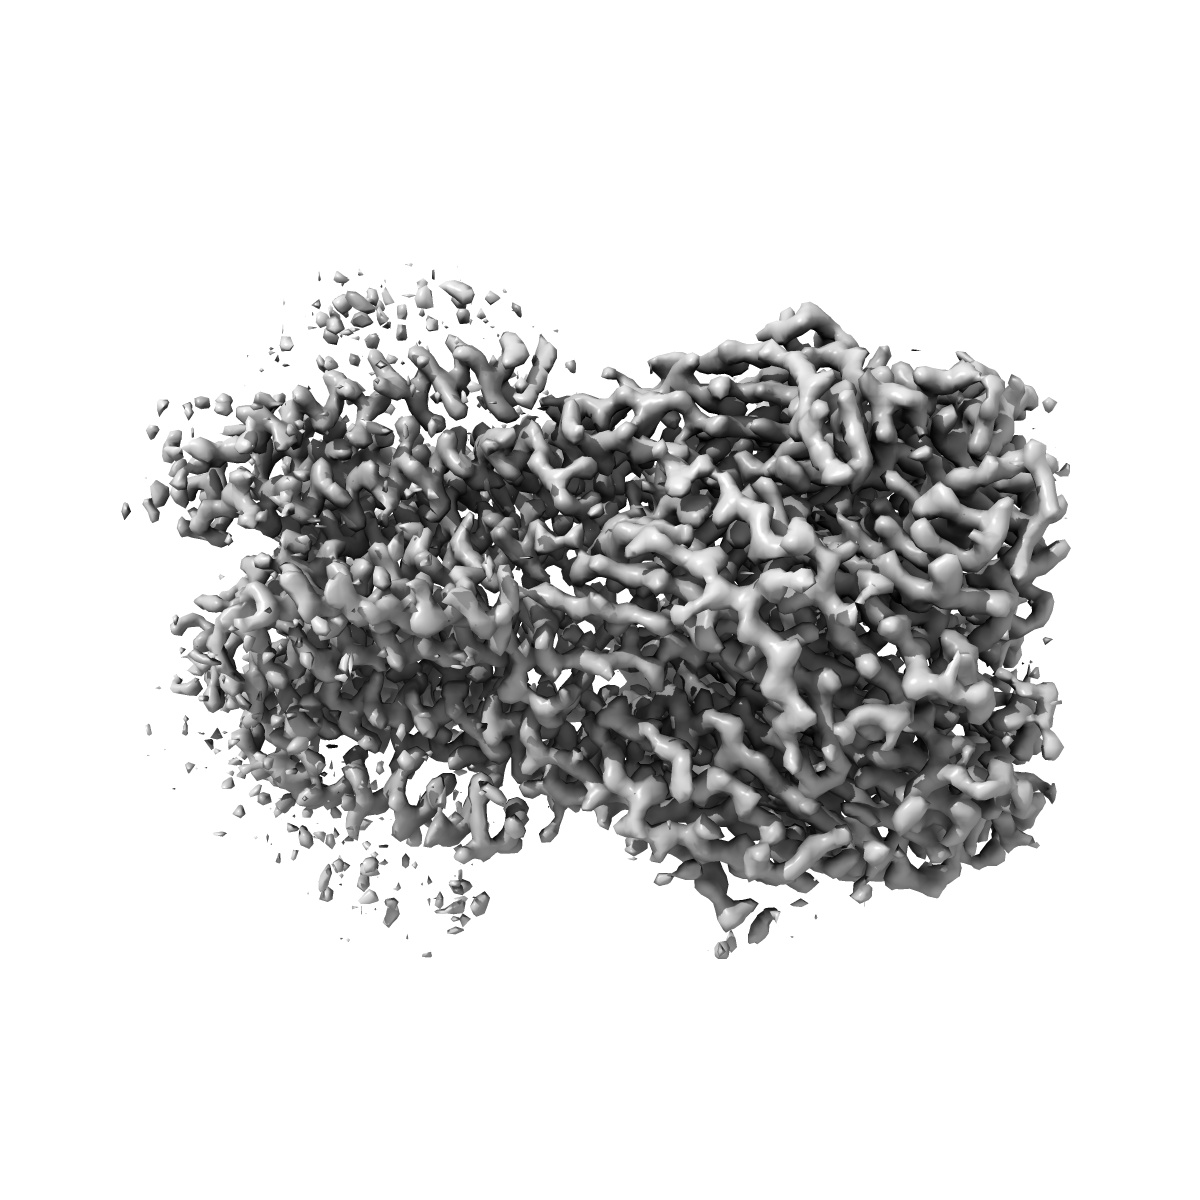

CryoEM structure of human full-length heteromeric alpha1beta3gamma2L GABA(A)R in complex with alprazolam (Xanax), GABA and megabody Mb38.

Single-particle3.26 Å

Sample: CryoEM structure of human full-length heteromeric alpha1beta3gamma2L GABA(A)R in complex with alprazolam (Xanax), GABA and megabody Mb38.

GABAAreceptor signalling mechanisms revealed by structural pharmacology.